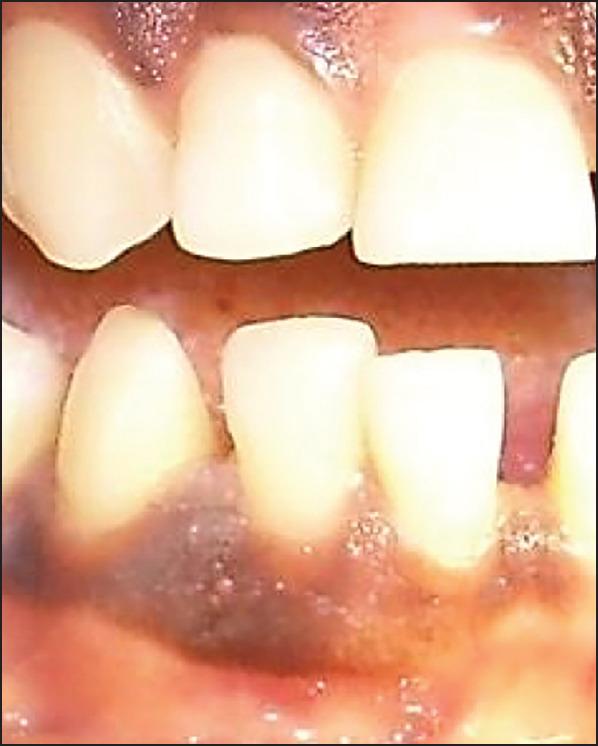

This case report describes the treatment of a double root fracture of a lateral mandibular incisor and its follow- up over 3.5 years. The reason for the consultation was a tooth mobility following a fall that had occurred 2 days earlier. A test of pulp vitality for tooth 42 was positive. Periodontal probing at the level of the gingival sulcus confirmed the intactness of the epithelial attachment. Retro-alveolar radiographic examination revealed a double root fracture of tooth 42. A semi-rigid extra-coronal splinting was performed and a light grinding of the incisal edge of tooth 42 was then carried out in light of the dislocation of the coronal fragment, and the occlusion was checked with a strip of articulating paper. The outcomes at 6 months revealed that pulp vitality was still preserved, consolidation of the apical fracture had occurred, and the coronal root fracture was starting to heal. The 1-year, 2-year and 3-year follow ups revealed preserved pulp vitality, an absence of a fracture line in apical images, and no root resorption. This case report provides evidence for the preservation of vitality in the setting of a double root fracture.

本病例报告描述了一例下颌侧切牙双根骨折的治疗及其3.5年的随访情况。会诊原因是2天前摔倒后牙齿松动。对42号牙的牙髓活力测试呈阳性。在龈沟水平进行牙周探诊证实上皮附着完整。牙槽后位X线检查显示42号牙双根骨折。进行了半刚性冠外夹板固定,然后根据冠部骨折块的移位情况对42号牙的切缘进行了轻度打磨,并用一条咬合纸检查了咬合情况。6个月时的结果显示牙髓活力仍然保留,根尖骨折已愈合,冠根骨折开始愈合。1年、2年和3年的随访显示牙髓活力保留,根尖影像中无骨折线,且无牙根吸收。本病例报告为双根骨折情况下保留牙髓活力提供了证据。